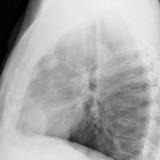

Case 9 Thymoma Lat

Date: 04/04/2010

Views: 3177